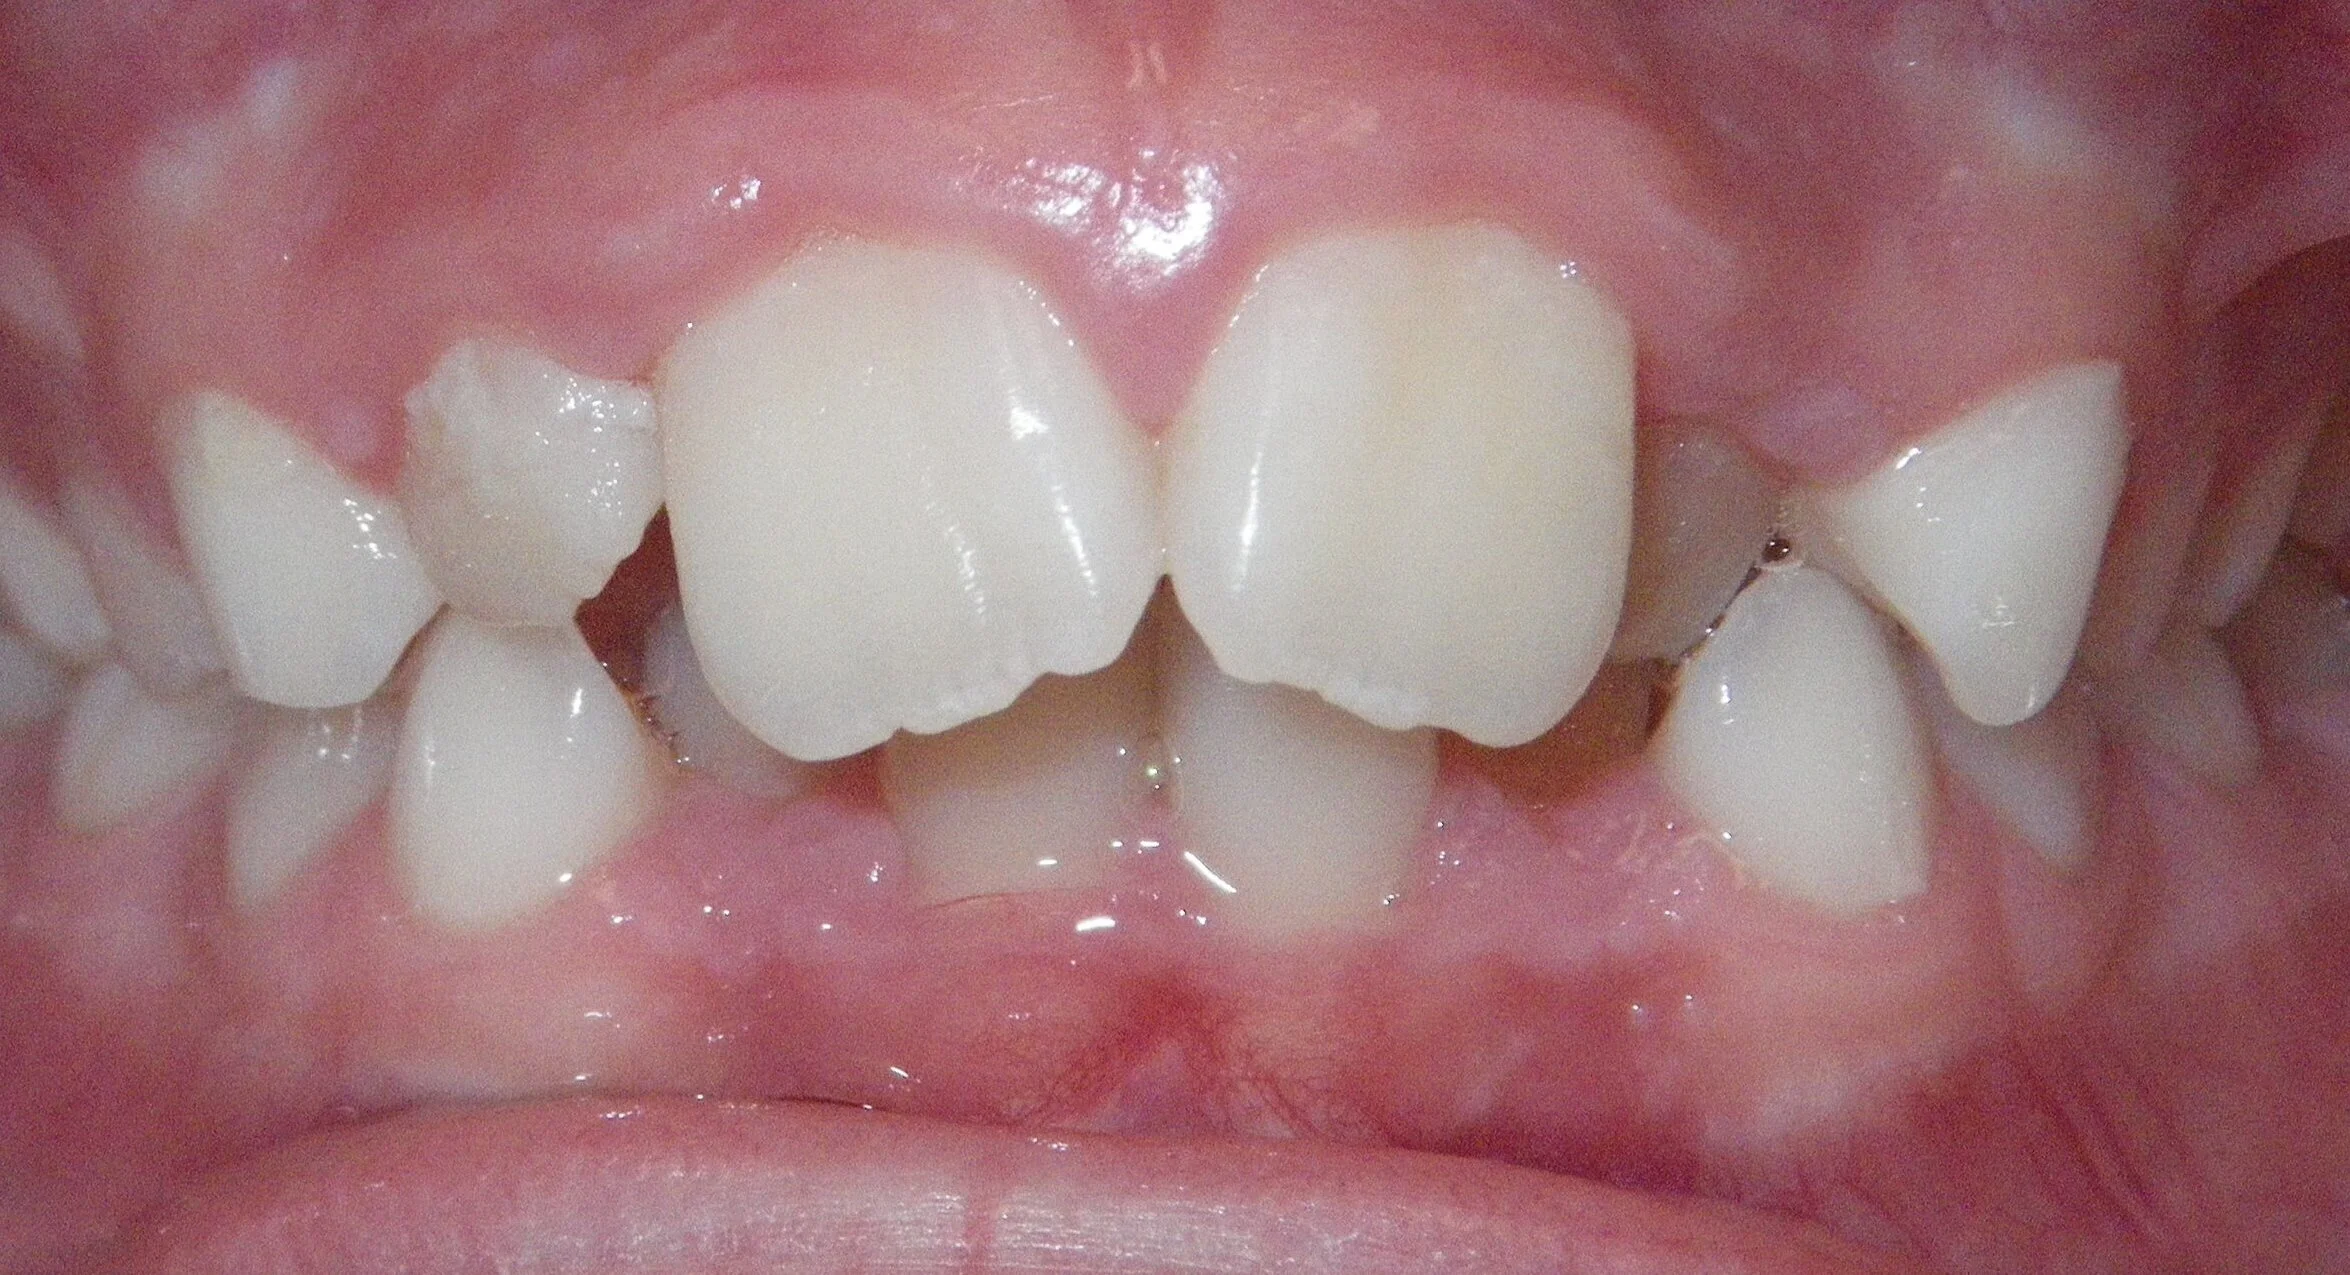

Phase I can be used to help change unfavorable growth or to make room so all the adult teeth have room to erupt. Here, we used Phase I to make room for the adult canines and followed up with Phase II treatment to a get a great esthetic and functional result!